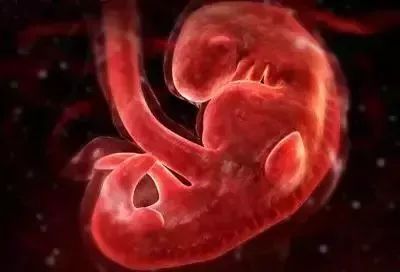

三个月:胎儿的身体为7-9厘米,重约20克,与4-7周相比,胎儿增加了3.4倍以上,躯干和腿部全部发育,头部明显较大,下颚和颊部发达,更重要的是鼻子、嘴唇、根。声带已经长了,脸部更像脸部,眼睛已经被比较了。眼睑生长。它能对外界刺激作出反应。如果你用手戳你的胃,它甚至会移动,但在几周内,你就感觉不到他的活动。胎儿肠生长很快,其中一些进入脐带。他们开始转移到腹腔。胎儿的肾脏分泌尿液进入膀胱。

四个月:胎儿长度约13~17 cm,体重约125克。骨骼系统进一步发育,胎盘完全形成,胎儿肢体活动,母亲感觉胎儿运动,肌肉发达。虽然胎儿的毛发还没有出现,他的头皮结构已经开始发育。虽然他仍然闭上眼睛,他的眼球可以缓慢移动,甚至开始有长长的指甲。